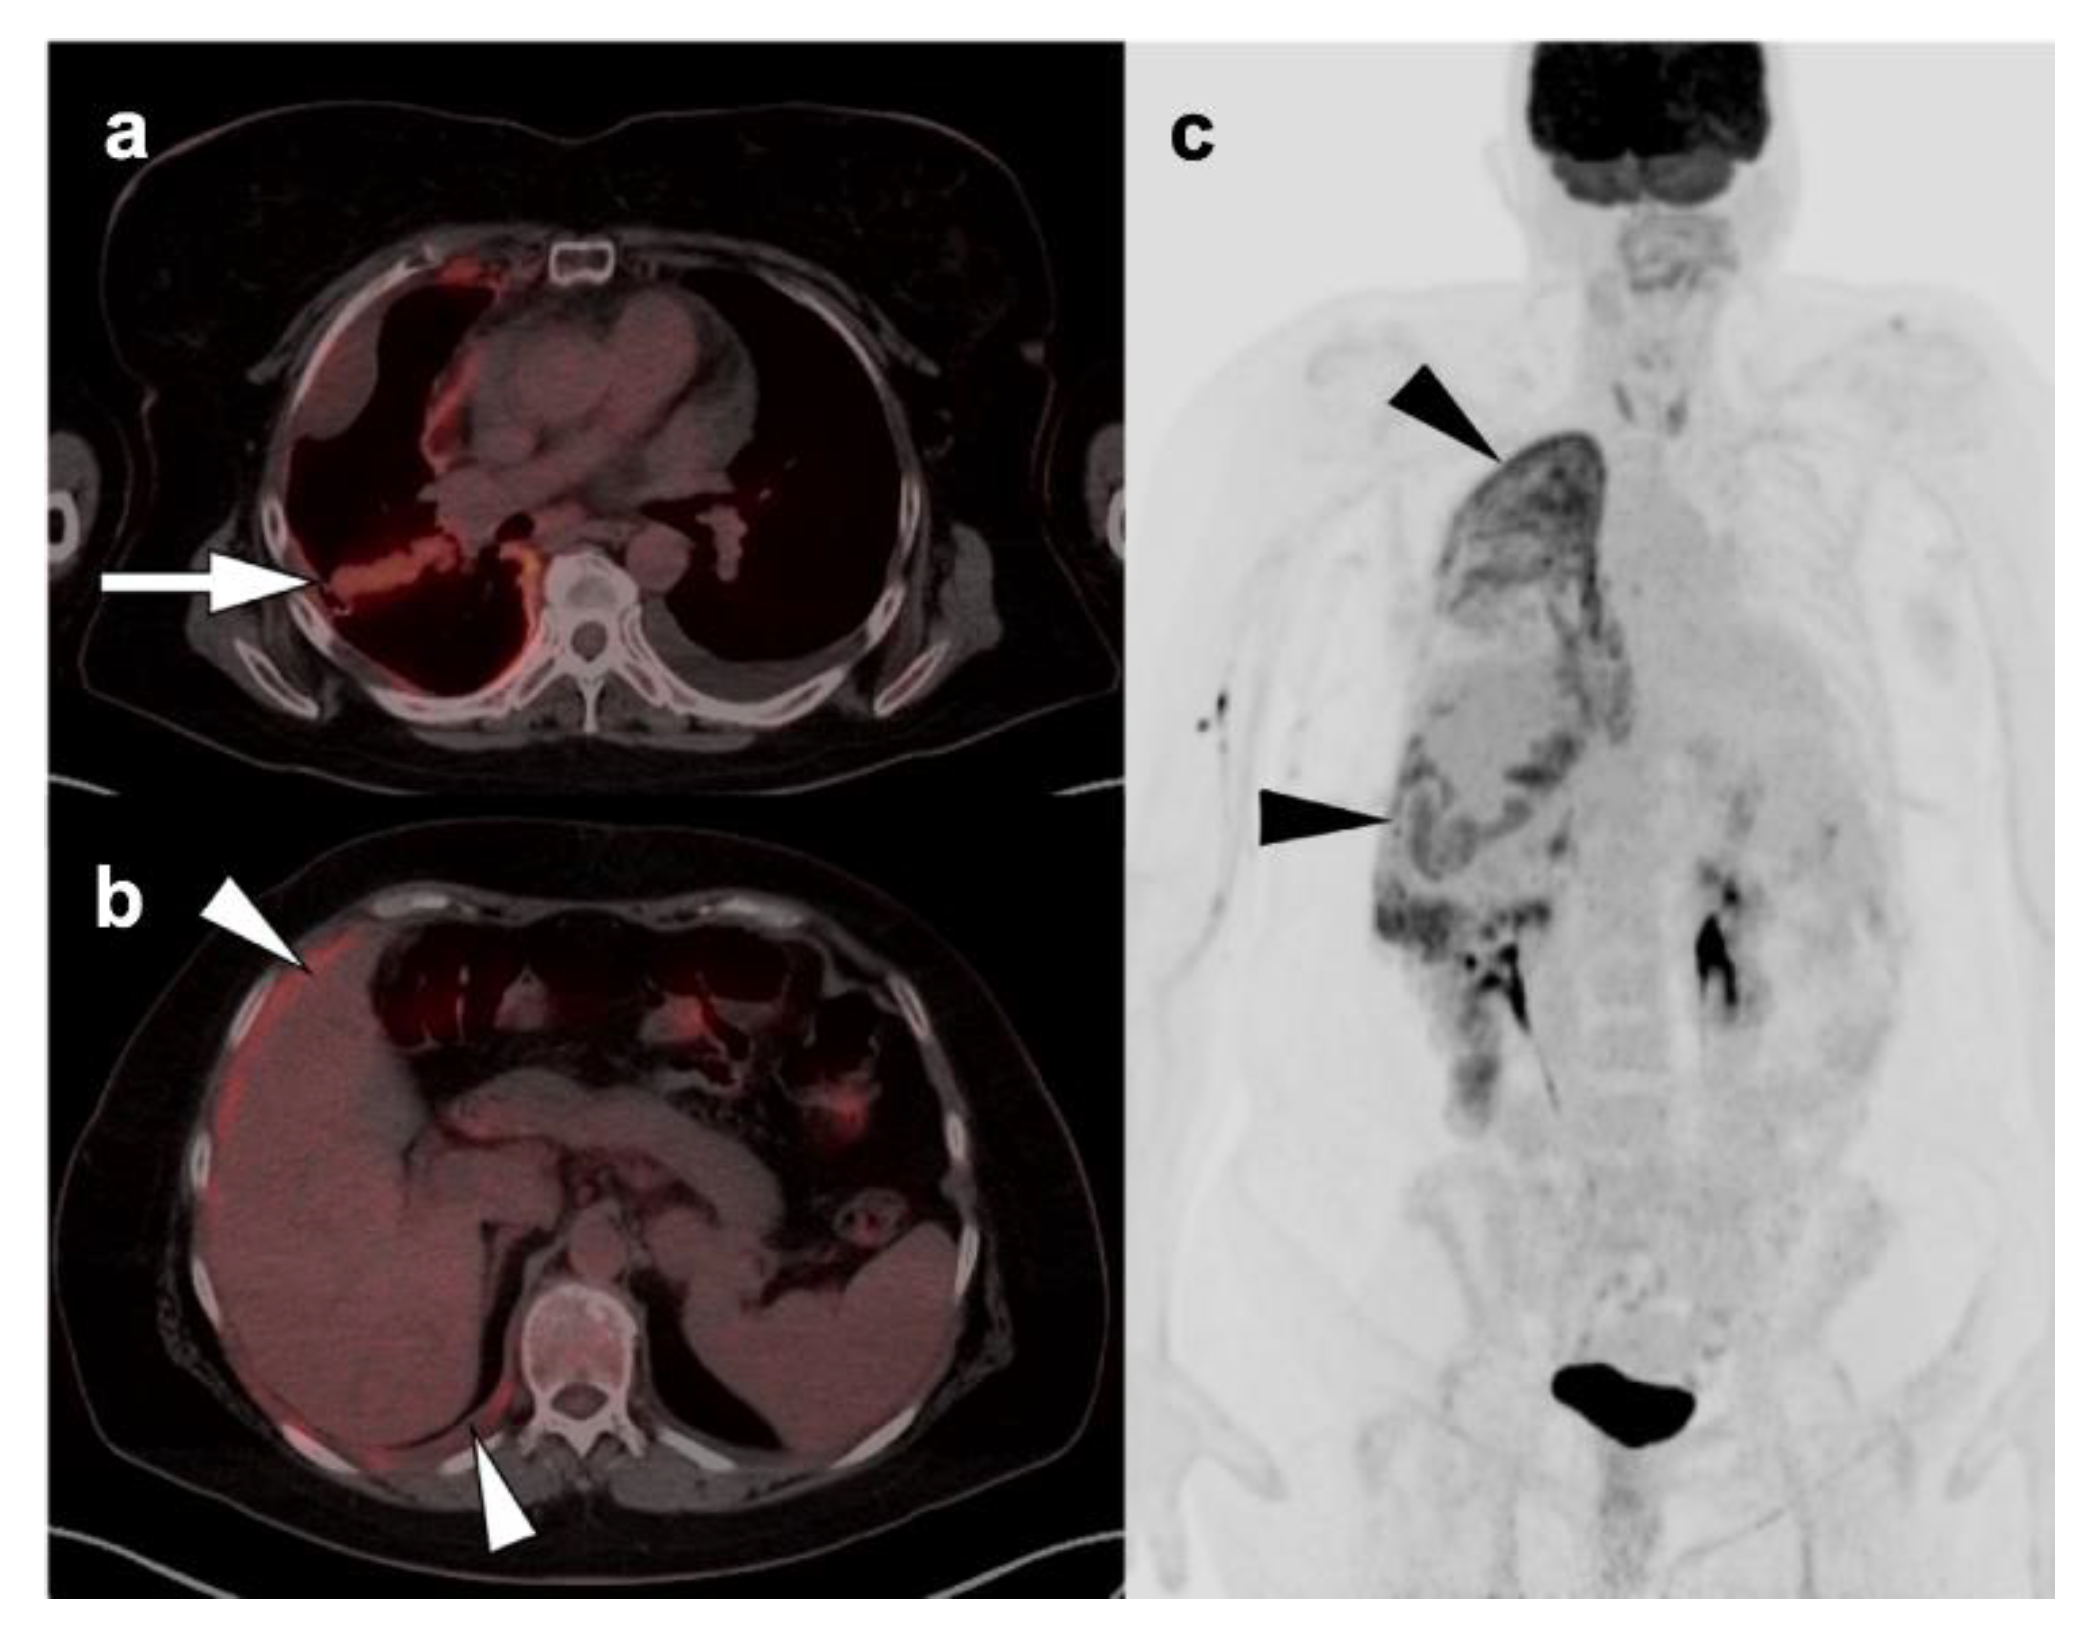

Nearly half of all patients with NSCLC have distant metastatic disease at initial diagnosis and identification of distant metastases is of major importance in the management and prognosis. Additionally, among patients who have been treated with radical and supposedly curative therapy, approximately 20% are likely to develop recurrent disease due to undetected foci of metastasis at initial M staging. Distant metastases are most commonly seen involving the brain, skeleton, liver, and adrenal glands in descending order of frequency (Figure 10) [31]. Traditional evaluation for distant metastatic disease includes CT scans of chest, abdomen, and pelvis, brain imaging with CT or MRI and bone scintigraphy [2]. However, FDG PET-CT has been shown to be great utility in M staging of the patients with NSCLC, specifically if the patients present with clinical manifestations of metastatic disease. Additionally, FDG PET-CT has been shown to provide more pertinent information during the preoperative assessment than is CT alone, except in the assessment of brain metastases, in a situation where the two modalities yield similar results [32]. For staging mediastinal lymph nodes, diffusion-weighted imaging MRI (DWI) and FDG PET-CT showed similar performance in staging of mediastinal lymph nodes, supporting the idea that DWI may offer an alternative to FDG PET-CT in some cases [33].

2.4. Small Cell Lung Cancer

Small cell lung cancer (SCLC) is an extremely aggressive tumor type which accounts for about 10–15% of all lung cancer cases [38,39]. It originates from neuroendocrine precursor cells and is characterized by rapid growth and early metastatic potential, with approximately 70% of patients presenting initially with metastases [40]. Up to 10–25% of patients with SCLC have brain metastases at the time of initial diagnosis and an additional 40–50% will develop brain metastases during the course of their disease. Although SCLC is usually chemo-sensitive in the early stages and sensitive to radiation therapy, most patients with SCLC will experience recurrent disease leading to death. Over 95% of patients with SCLC are either current or former smokers [2]. According to the Veterans Administration Lung Group’s criteria, SCLC has been traditionally divided into two stages—a binary system of staging—limited disease and extensive disease [41]. Limited-stage disease SCLC (LD-SCLC) is disease confined to ipsilateral hemithorax, mediastinum (including contralateral mediastinal nodes), and ipsilateral supraclavicular nodal involvement, which can be encompassed within a single radiation field (Figure 11) [42]. Extensive-stage disease SCLC (ED-SCLC) is spread beyond the ipsilateral hemithorax including hematogenous metastatic disease and presence of malignant pleural or pericardial effusion (Figure 12) [39,43]. Standard therapy for patients with LD-SCLC includes chemotherapy in conjunction with radiation therapy. Due to high potential for developing brain metastases in this group of patients, palliative cranial radiation is also indicated to increase overall survival. In ED-SCLC, only systemic chemotherapy is considered, as a palliative treatment, because long-term survival in these patients is rare [43,44]. According to the more recently adopted AJCC (American Joint Commission on Cancer) TNM staging system 8th edition, there is no significant difference between NSCLC and SCLC in the staging system [26]. The NCCN Panel adopted a combined approach for staging SCLC using both the AJCC TNM staging system and the VA scheme for SCLC. In applying the TNM classification to the VA system, the so-called limited-stage SCLC is defined as stage I–III (any T, any N, and M0, respectively), which can be effectively treated with definitive radiation therapy and extensive-stage SCLC is defined as stage IV (any T, any N and M1a/b) or T3–T4, harboring multiple lung nodules or tumor volume that is too large to be encompassed in a tolerable radiation plan/field.